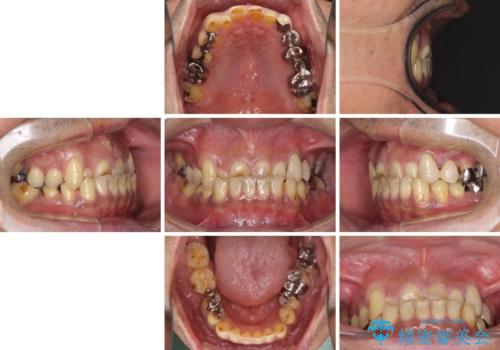

- すり減った前歯や奥歯の銀歯を気にして来院された患者様です。

骨格的な反対咬合により上顎前歯の先端が顕著にすり減っている状態でした。

奥歯の欠損が散見されており、銀歯の装着されている歯も多いため、ワイヤー矯正にて歯列を調整し、その後オールセラミッククラウンにて補綴治療を行うこととしました。

反対咬合改善には奥歯の咬み合わせをしっかりと改善させることが必要となりますが、奥歯に欠損が多いため、矯正治療が難航することが予想されます。

矯正治療は想定通り長期化しましたが、しっかりと奥歯の咬み合わせを向上させて前歯の被蓋を改善させることができました。

目立つ銀歯やすり減った前歯がセラミッククラウンとなり、患者様には大変満足していただけました。